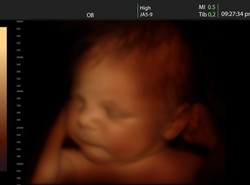

W lipcu zespół lekarzy przeprowadził pierwszą z wielu operacji, które pomogą przywrócić twarz Olafowi. Chłopiec urodził się z rzadką wadą genetyczną, która spowodowała, że nie ma oczu i nosa.

W "Dzień Dobry Wakacje" o operacji i rokowaniach małego pacjenta opowiedzieli: chirurg szczękowy dr n. med. Maciej Jagielak, specjalista chirurgii i urologii dziecięcej Piotr Pogorzelski, chirurg plastyczny Joanna Jutkiewicz-Sypniewska.